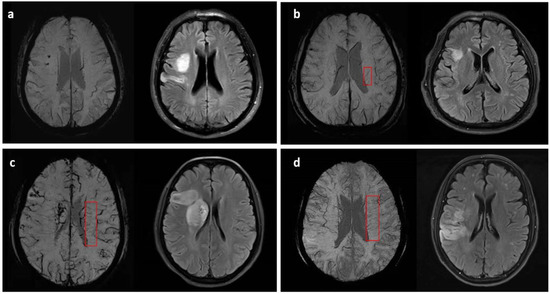

2.4. Assessment of DMVs Grade and Other Neuroimaging Characteristics